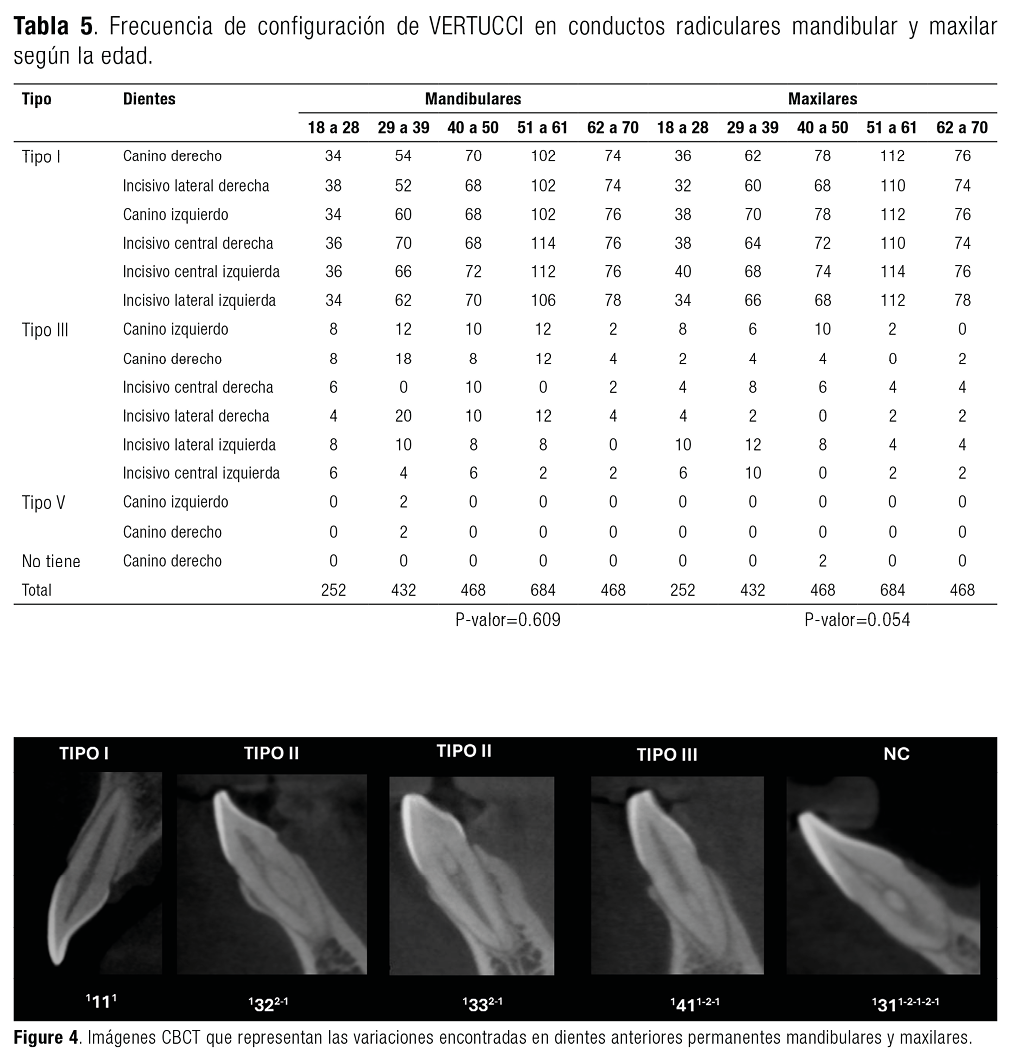

Se accedió a un total de 384 imágenes CBCT de pacientes a través de datos retrospectivos. Las muestras estudiadas fueron pacientes oriundos de Perú. Según Vertucci (Figure 2) y el nuevo sistema de clasificación de Ahmed (Figure 3). En la Tabla 1, se muestra la configuración de conductos según la clasificación de Ahmed y Vertucci cuyos resultados presentaron una mayor frecuencia en la clasificación ¹MI¹ y tipo I en el maxilar superior, seguidos de la clasificación ¹MI¹‐2‐¹ con el tipo III en el maxilar inferior, así mismo, se encontró dientes en la que se utilizó la codificación ¹MI¹‐²‐¹‐²‐¹, que fue un código único que se aplicó utilizando el último sistema introducido por Ahmed et al. Y este se observó en el canino derecho superior, el incisivo central derecho e inferior izquierdo, así como en el canino inferior izquierdo. El valor de chi cuadrado obtenido en el maxilar fue 0.016 y en mandibular fue de 0.001 cuyo valor es <0.05 lo que sugiere que hay relación estadísticamente significativa entre los dientes maxilares y mandibulares, así mismo, en la clasificación de Ahmed, el valor de chi cuadrado obtenido fue 0.001 en maxilar y mandibular, cuyo valor es <0.05 lo que sugiere que hay relación estadísticamente significativa entre los tipos de dientes maxilares y mandibulares y la clasificación de Vertucci.

En la Tabla 4 y Tabla 5, se muestra que la codificación ¹MI¹ y Vertucci Tipo I tiene mayor afinidad por los pacientes con edades que oscilan entre (50-70 años) en los dientes de ambos maxilares, seguido de ¹MI¹‐²‐¹ con el Tipo III de Vertucci que están presente tanto en mandibular como maxilar en las edades correspondientes a (18-39) años. Luego,¹MI¹‐²‐¹‐²‐¹ presente en edades 18-28 años en incisivos central inferior derecho e izquierdo, seguido de casos en los que se encuentran en edades de 40-50 años en el canino derecho. Asimismo, se observa que el ¹MI¹‐², perteneciente a Vertucci V, está presente en menor cantidad en las edades de 29 a 39 años, tanto en el canino izquierdo como en el derecho. El valor de chi cuadrado obtenido para los tipos de dientes maxilares y la clasificación de Ahmed en relación con la edad fue de 0.105, cuyo valor es mayor a 0.05, lo que sugiere que no hay una relación estadísticamente significativa entre estas variables. De igual manera, el valor de chi cuadrado para los tipos de dientes mandibulares y la clasificación de Ahmed en relación con la edad fue de 0.376, también mayor a 0.05, indicando que no existe una relación estadísticamente significativa. En cuanto a la clasificación de Vertucci, el valor de chi cuadrado obtenido para los tipos de dientes maxilares fue de 0.054, superior a 0.05, lo que sugiere que no hay una relación significativa, al igual que el valor de chi cuadrado de 0.609 para los tipos de dientes mandibulares y la clasificación de Vertucci en relación con la edad, que también es mayor a 0.05, lo que confirma la ausencia de una relación estadísticamente significativa (Figure 4).